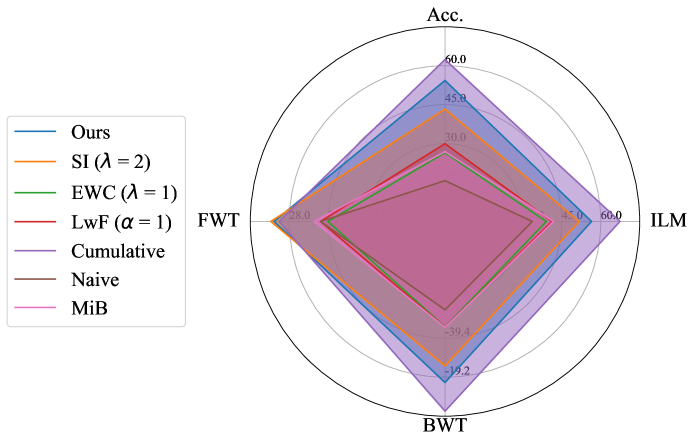

Performance comparison with others: For the considered medical applications, the primary concern will not be on improving zero-shot performance (FWT) but rather on minimizing forgetting (BWT) and enhancing the average DSC of the model (ACC and ILM). While FWT is reported for completeness, our analysis emphasize ACC, ILM, and BWT. Table 2 presents the ACC, ILM, BWT, and FWT values for all methods across sequences S1, S2, S3, and S4. Across all sequences, CL approaches (GDumb, Replay, MiB, LwF, SI, EWC, and the proposed method) mostly outperform naive training, highlighting the importance of mechanisms to mitigate catastrophic forgetting in UNet-based segmentation tasks. Further, as expected, approaches storing past data partially (Replay, GDumb) or fully (cumulative, joint training) show higher performance compared to methods (naive, MiB, LwF, SI, EWC, and the proposed approach) with no access to past exemplars. When comparing the proposed method to other buffer-free approaches (MiB, LwF, SI, EWC), it consistently achieves superior performance in all the sequences S1, S2, S3, and S4. Unlike these existing CL methods, which penalize large deviations from previously learned weights through response-level regularization terms in the training loss, the proposed approach introduces a drift-based dynamic penalization factor along with a latent-level regularization. This drift-based dual distillation allows for more effective mitigation of catastrophic forgetting. The proposed method shows a positive gain in (ACC, ILM, BWT) over best performance achieved among state-of-the art buffer-free approaches (blue colored in Table 2). Specifically, we observe an improvements of (25.51%, 9.23%, 34.34%) in S1, (6.57%, 25.28%, 31.85%) in S2, (4.85%, 11.02%, 40.15%) in S3, and (7.67%, 10.65%, 17.62%) in S4. For intuitive visualization, radar plots for S1, S2, S3, and S4, comparing cumulative, naive, the best-performing buffer-free methods, and the proposed approach are provided in Fig. 6 of Appendix.

Appendix B Radar Plot based Comparison

For intuitive visualization, Fig. 6 provides a radar plot comparing cumulative, naive, the best-performing buffer-free CL methods, and the proposed approach. In all the formulated dataset sequences, the proposed method demonstrates clear superiority over all other approaches except cumulative, which serves as the upper performance bound.